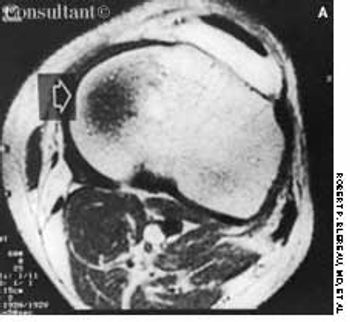

Back pain and weakness of both legs had bothered this 60-year-old woman for 1 week. Left breast cancer, stage 2, had been diagnosed 2 years before, and subsequently she underwent a lumpectomy followed by chemotherapy and radiation therapy.